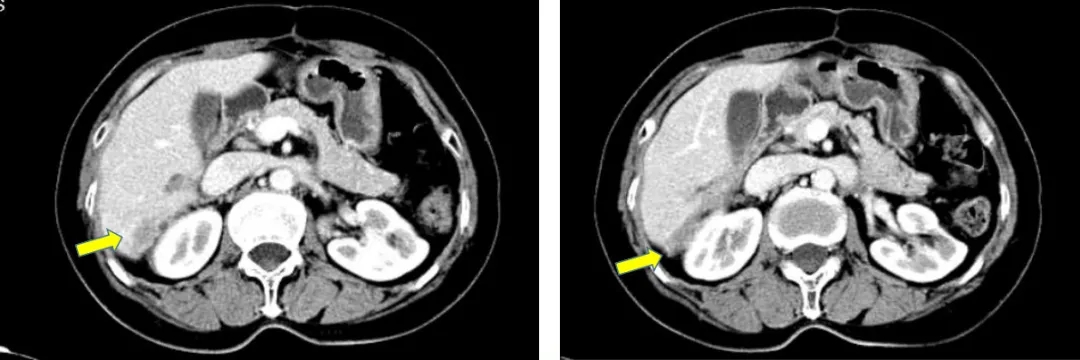

2017-10-26当地查CA125水平为46.3U/ml,2017-12-4我院查CA12水平为110.9U/ml,CT显示肝肾间隙及右肝包膜下片状影较前增大,考虑疾病复发。

CT检查结果